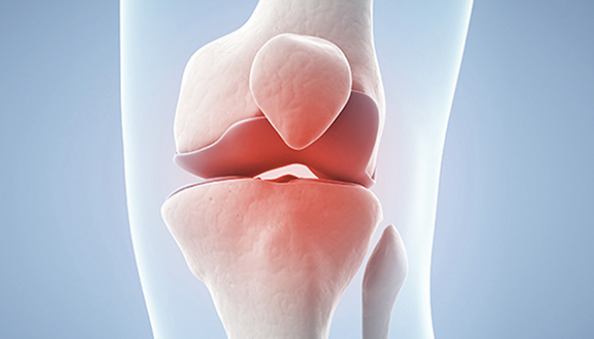

글루코사민은 우리 몸의 연골을 이루는 필수성분으로 관절에 탄력성을 주고, 관절 강도를 높이는 역할을 합니다.

연골의 필수 성분인 글루코사민은 우리 몸에서 원래 스스로 생성되는 성분입니다. 그러나 나이가 들어 가면서 글루코사민 생성 능력은 현저히 감소하게 됩니다. 이에 따라 자연스럽게 관절연골의 완충 능력은 나빠지게 되고, 손상받기 쉬운 상태가 되어 버립니다. 그리고 이 손상이 염증을 유발합니다. 이것이 바로 관절염입니다.